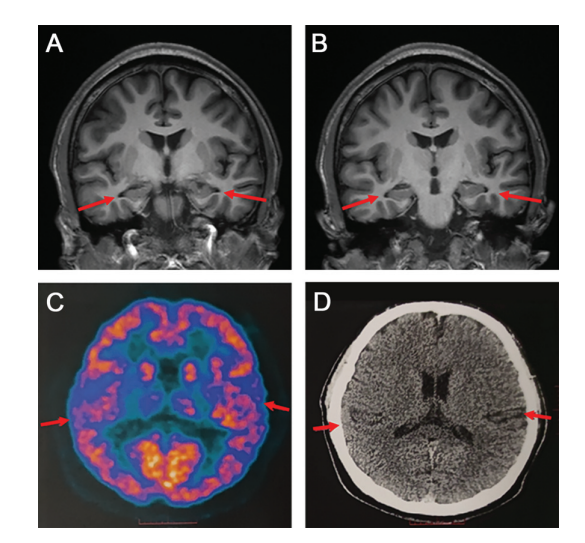

文中介绍,一名来医院就诊的19岁男孩,被临床诊断为阿尔茨海默症患者,这也是迄今为止最年轻的患者。

根据研究小组提供的资料显示,该患者在就诊前两年开始出现在学习时注意力难以集中,一年后,短期记忆丧失明显,无法回想起前一天发生的事或个人物品的存放位置,阅读困难,反应缓慢。

随着病程进展,记忆力进一步下降,经常丢失个人物品,记不清自己是否吃过饭,难以完成学习内容和老师布置的作业。由于记忆力下降严重,他的学习成绩从之前的中等以上水平下滑到班内末位,无法完成学业,不得不从高中退学。